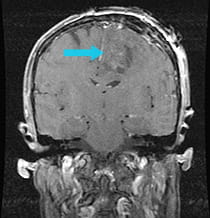

Pre-surgical scan shows metastasis on the frontal lobe. Post-surgical scan shows the successful removal of tumor.

Post-surgical scan shows the successful removal of the tumor following minimally invasive Neuroendoport Surgery.

The metastatic tumor was removed using the minimally invasive Neuroendoport, and the patient began making words in the recovery room.

The patient subsequently regained strength in her arm and leg, and her speech eventually returned to nearly normal function over a period of months.